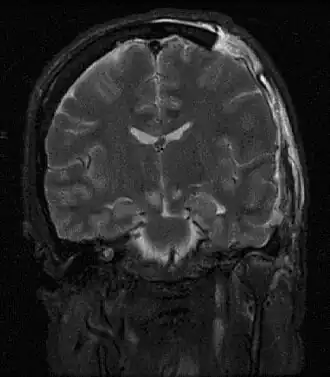

Description de l'image Brain herniation MRI.jpg.

En médecine, on parle d'engagement cérébral lorsqu'il y a déplacement d'une structure cérébrale au travers d'un orifice naturel.